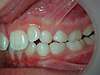

CAS ENFANT 1

Décalage des mâchoires et dents du haut très avancées

Patiente présentant un gros décalage entre les mâchoires du haut et du bas, avec les dents du haut très avancées.

Cas traité avec un appareil de correction des mâchoires, puis des bagues. Aucune opération chirurgicale n’a été réalisée.

Après